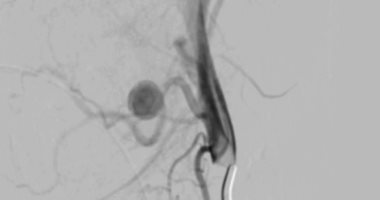

نجاح الفريق الطبي في السيطرة على النزيف

ذكر الدكتور أحمد كمال، المدير التنفيذي للمستشفيات الجامعية، أنه تم تجهيز وحدة القسطرة على الفور، حيث نجح الفريق الطبي في غلق التمدد الشرياني باستخدام حلزونات دقيقة عبر القسطرة التداخلية، مما أسهم في السيطرة الكاملة على النزيف دون الحاجة لجراحة تقليدية وتقليل احتمالات المضاعفات.